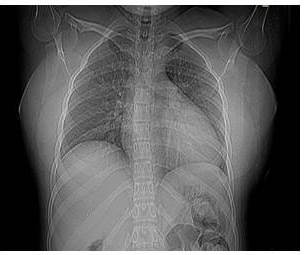

En la radiografía simple de tórax posteroanterior y lateral, se evidencia imagen radiopaca de apariencia redondeada, de unos 4 cm de diámetro, localizada a nivel del tercer (3er) arco costal posterior izquierdo (Figura 1).